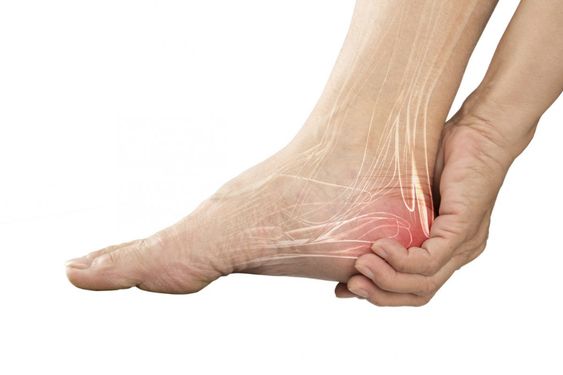

족저 근막염 증상 2. 뒤꿈치 통증

통증 부위는 대부분 발뒤꿈치 안쪽 또는 중앙 부위예요.

서있거나 걷는 시간이 길어질수록 욱신거리는 통증이 더 심해질 수 있습니다.3. 장시간 앉은 뒤 다시 일어설 때 통증